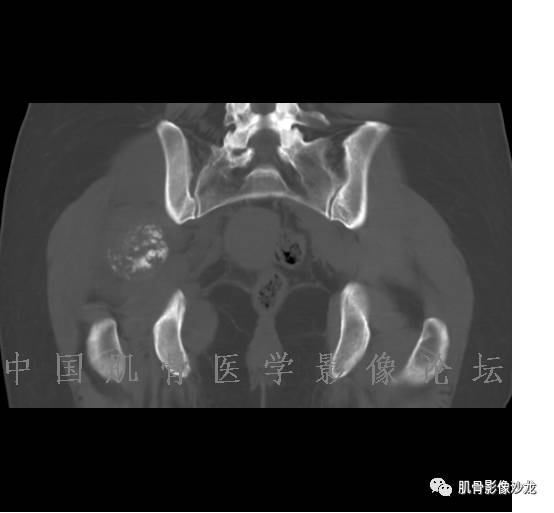

患者2月前无明显诱因下感右腿疼痛、麻木,疼痛呈持续性,发作时无法行走,休息后可缓解。当时无明显肿块,患者遂至当地医院就诊,查X片见右髂骨骨质破坏。6周前患者自觉右髋部渐大肿块,初肿块较小,后肿块逐渐增大,现肿块约12*10cm大小,有压痛。患者遂至我院就诊,查MRI:右髂骨异常信号,伴软组织肿块。ECT、肺CT未见转移。现患者为求进一步治疗,门诊拟“右髂骨肿块 ”收治入院。 患者发病来,神清,精神可,胃纳夜眠可,二便无殊,体重无明显变化。

1、软骨肉瘤可以有膨胀性骨质破坏(病例3,4),可以有溶骨性骨质破坏(病例2),局部皮质因为破坏变薄,中断 ;

2、软骨基质T2WI高信号,软骨小叶分叶状,也就会出现高老师提到的骨内膜扇贝形压迹。一般认为骨内膜扇贝形压迹超过骨皮质厚度的2/3是软骨肉瘤在长管状骨的特征性表现。如上图。3、软组织肿块或肿胀;

4、 钙化,环形,弓形,边缘模糊 ;

5、增强后进行性延迟,不均匀分割状强化, 会强化的纤维间隔,软骨小叶不会强化,关于老师们说到的钙化,软骨肉瘤不一定会有钙化 。

2、软骨肉瘤的发病部位排名:最好发部位为髂骨,其次股骨、肱骨和脊柱。